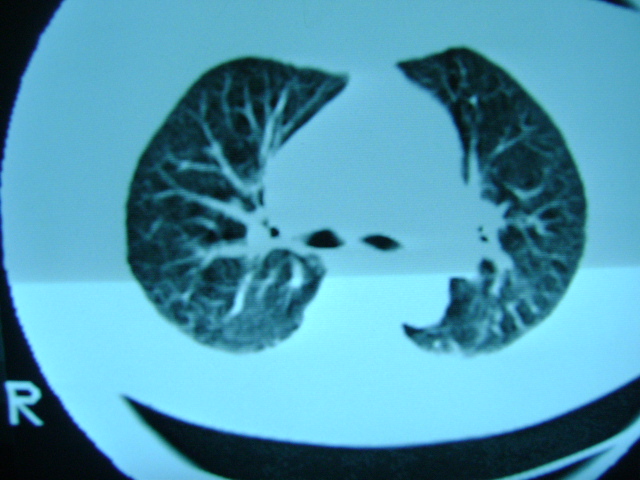

朋友的母亲,56y,咳嗽三个月,感觉左肺门不对,请大家给点意见

左肺门还可以吧

左肺门未见异常!

肺内应该存在感染

慢支 !不放心可追踪复查。